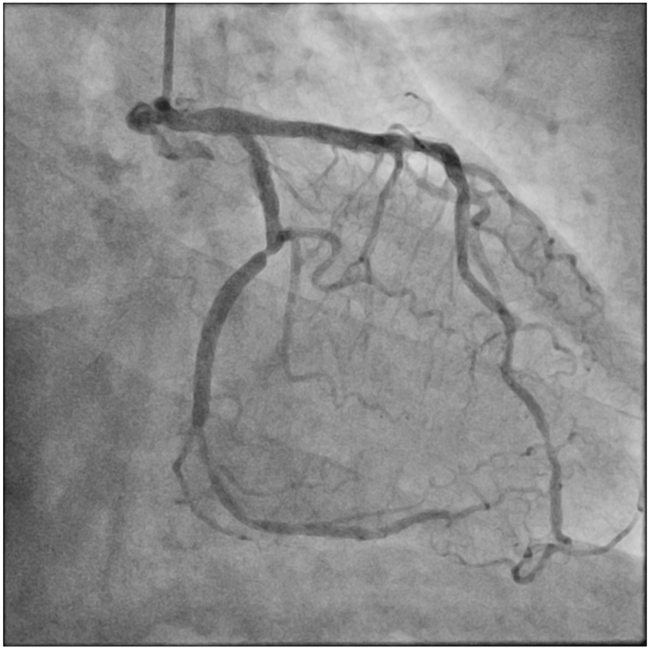

A 71-year-old man who had undergone percutaneous transluminal coronary angioplasty (PTCA) in 2013 was admitted for unstable angina. Coronary angiogram showed 2 de novo lesions at the proximal and distal left circumflex artery (LCX) (Figure 1A). PTCA was performed transradially via a 6-French (Fr) sheath. With a 6-Fr extra-backup 3.5 guide catheter engaging to the left main coronary artery (LM), a 2.5 x 18-mm drug-eluting stent (DES) was delivered to the distal LCX lesion but was inadequate for complete lesion coverage (Figure 1B). During retrieval, the stent was found dislodged at the distal LM bifurcation (Figure 1C).

Distal small balloon retrieval was unsuccessful (Figure 1D). With the help of the Balloon-Assisted Guide-extension (BAG) system, the stent could be optimally positioned at the proximal LCX lesion by forward pushing with a 6-Fr Guideliner V3 catheter (Teleflex) and backward pulling by the small balloon (Figure 1E and F; Video). It was then deployed by sequential balloon dilatation with good expansion (Figure 1G and H). Another 2.5 x 24-mm DES was deployed at the distal LCX, which gave an excellent final angiographic result (Figure 1I and J).